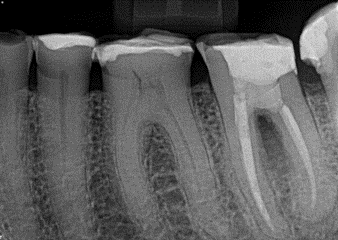

2. (Select ONE OR MORE correct answers)

What observation(s) can be made for tooth 4.7?